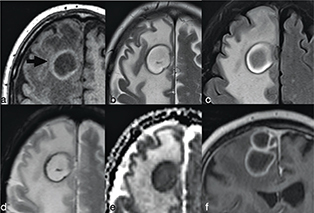

The abscess capsule is well-defined, smooth and complete. It shows a layered aspect, hypointense on FLAIR/T2-wi and hyperintense on T1-wi. The presence of collagen fibres and macrophages releasing free radicals are considered responsible for the short T1 and T2 of the rim due to their paramagnetic effect (Figure 2).7 The external low-signal rims on T2-wi could be useful to distinguish abscess from glioblastomas: in this case the rims, irregular or incomplete in the majority of cases, result from the store of haemorrhagic products surrounding the outer layer of the necrotic core.8

FIG 2. Nocardia Abscess in a 64-Year-Old Immunocompromised Man Presenting with Headache. A round lesion with thick capsule hyperintense on T1w (a) and hypointense on T2w/FLAIR-T2w (b–c) is shown. The lesion is characterised by a core of restricted diffusion (d–e). Typical ring-enhancement is present after intra-venous Gd administration; the coronal scan also reveals the presence of multiple lesions (f). A discreet amount of perilesional vasogenic oedema is present too (a–e).